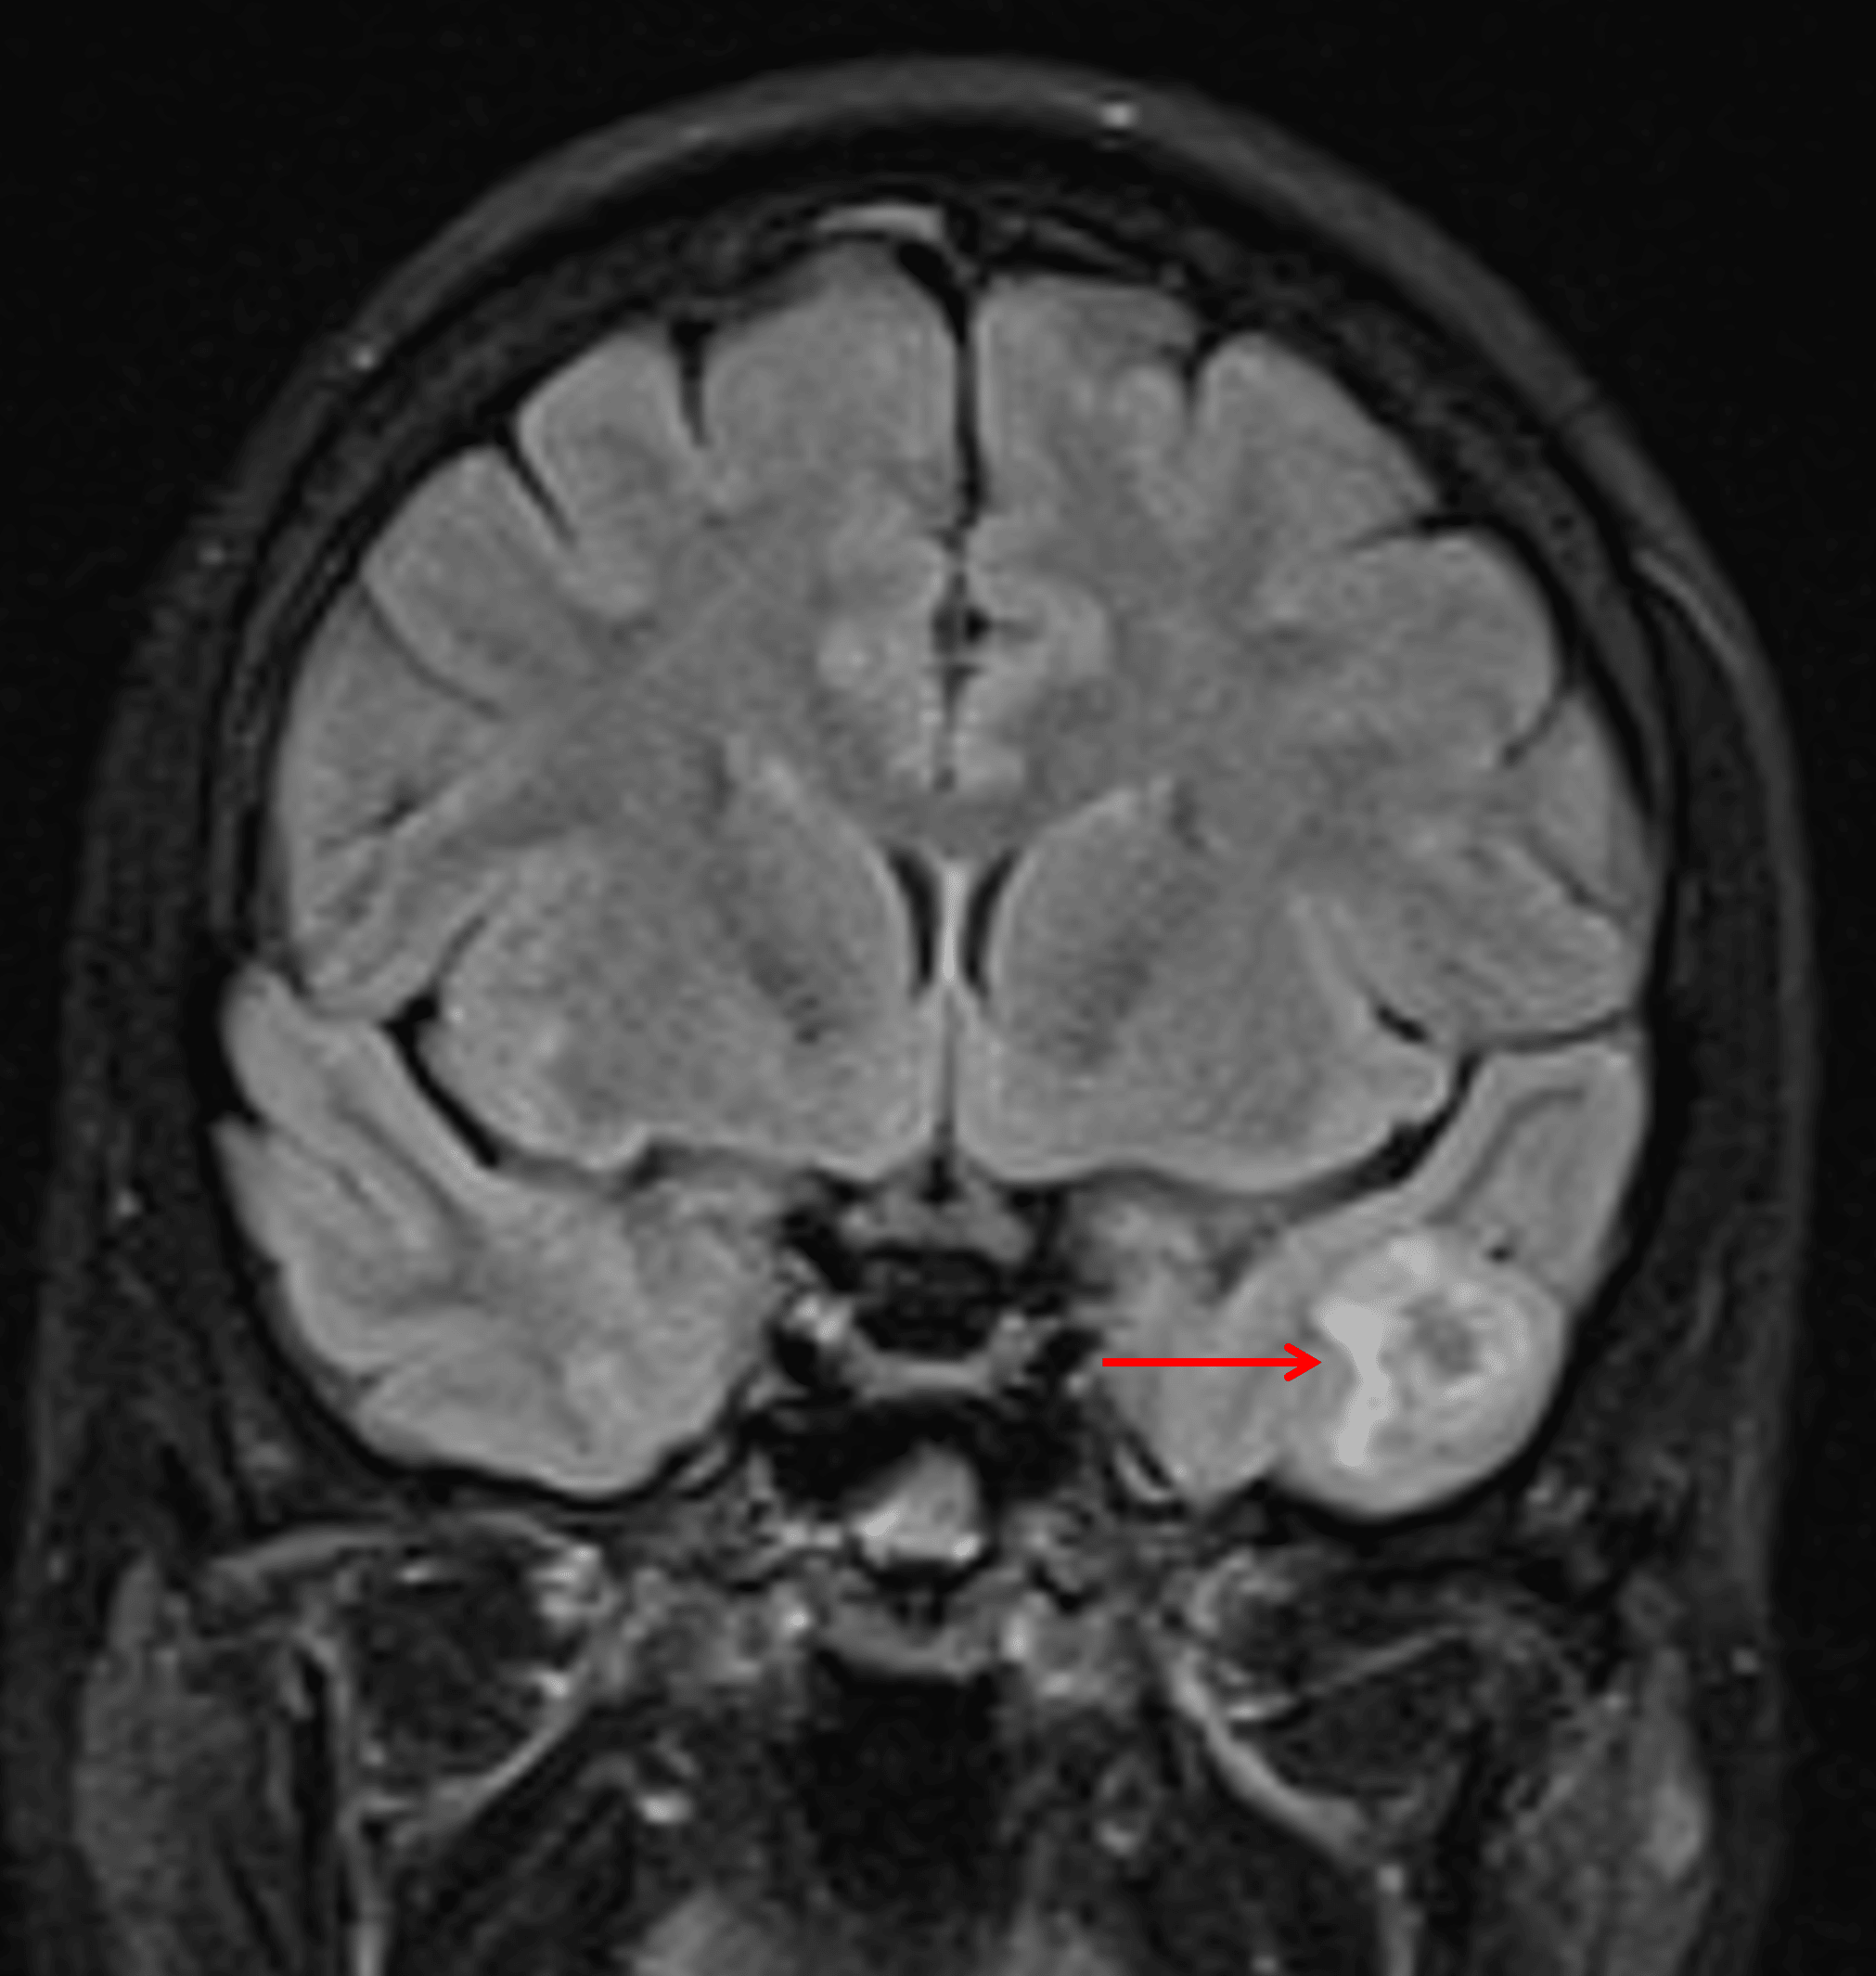

Small, mixed cystic and solid lesion in the inferior left temporal lobe with avid enhancement of the solid components (red arrow).

Minimal surrounding edema and mass effect (red arrow), which is typical for gangliogliomas.